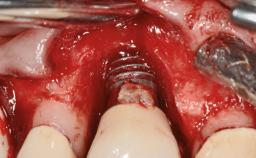

A 35-year old female patient was referred to the Department of Oral Surgery and Stomatology at the University of Bern, Switzerland, for examination of an implant site that had exhibited clinical signs of slightly delayed wound healing. In addition, the referring clinician found no evidence for a facial bone wall when she raised a flap to gain access to the implant for abutment connection. Four months earlier, she had inserted a bone-level implant in a single-tooth gap, where the lateral incisor had been extracted due to a chronic periapical lesion on the mesial aspect of the root. Implant placement was combined with simultaneous bone augmentation using deproteinized bovine bone mineral (DBBM, Bio-Oss®; Geistlich, Wolhusen, Switzerland) and a collagen membrane (Bio- Gide®; Geistlich), followed by primary wound closure. The patient also provided the postsurgical radiograph that displayed the implant with a 3.5-mm healing cap.